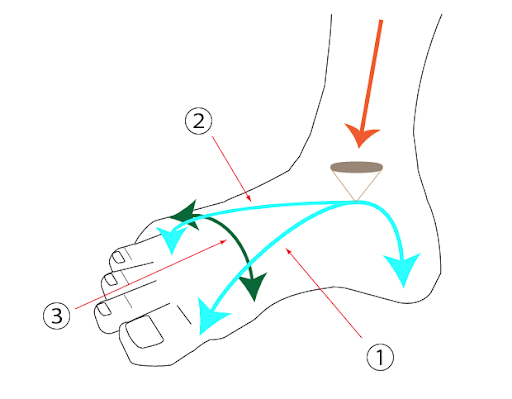

足底腱膜は足底のアーチ構造(いわゆる土踏まず)を支えており、足にかかる衝撃を吸収する役割や、吸収した衝撃を蹴り出す際のエネルギーとして活用する役割をしています。一時的走るなどのスポーツをするほど症状が強く出る場合もあります。

足底アーチの異常形成

足底部には3つのアーチが存在し、身体の重みや衝撃の吸収を行なっています。この足底部アーチが低下または上昇することで本来吸収されるべき以上の衝撃が足底腱膜にかかり、付着部や足底部に炎症を起こします。